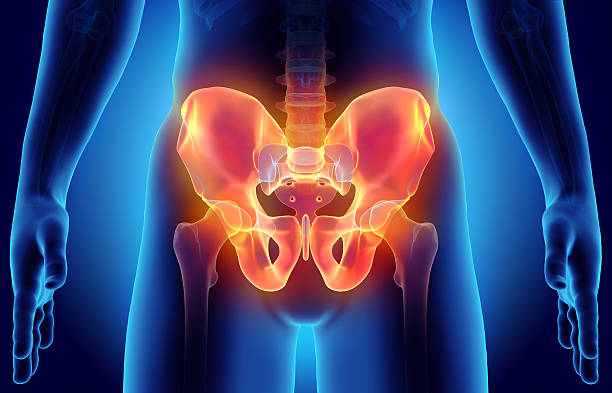

골반 통증 원인 - 골반 가운데

가운데로 오면 천골과 장골 사이의 천골 관절이 주로 문제가 됩니다. 골반이 뒤로 빠질 때 이 관절 부분에서 통증이 나타날 수 있으며, 이를 바로 잡아주는 치료가 필요합니다. 또한, 천골 주변에 기립근과 인대가 연결되어 있어 이 부위에도 통증이 나타날 수 있으므로 관련 스트레칭을 통해 개선할 수 있습니다.

골반 통증 원인 - 관절

골반 관절의 이상은 골반통증을 일으킬 수 있는 원인 중 하나입니다. 골반 관절의 이상은 관절의 염증이나 변형, 골절 등으로 인해 발생할 수 있습니다. 특히 장시간 동안 한 자세를 유지하거나 골반을 과도하게 사용하는 운동이 해당 관절에 부하를 주어 문제가 생길 수 있습니다.